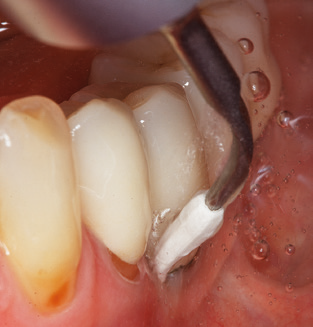

Naturalmente, anche i consigli di lavoro per la pulizia delle superfici degli impianti sono indispensabili per SPT nei pazienti dotati di impianti. L'inserto per la pulizia dell'impianto in questo casoi è caratterizzato dal suo design affusolato ed esagonale. Questo design consente una penetrazione leggera e atraumatica nella tasca perimplantare e mostra buone prestazioni di pulizia (Fig. 7).